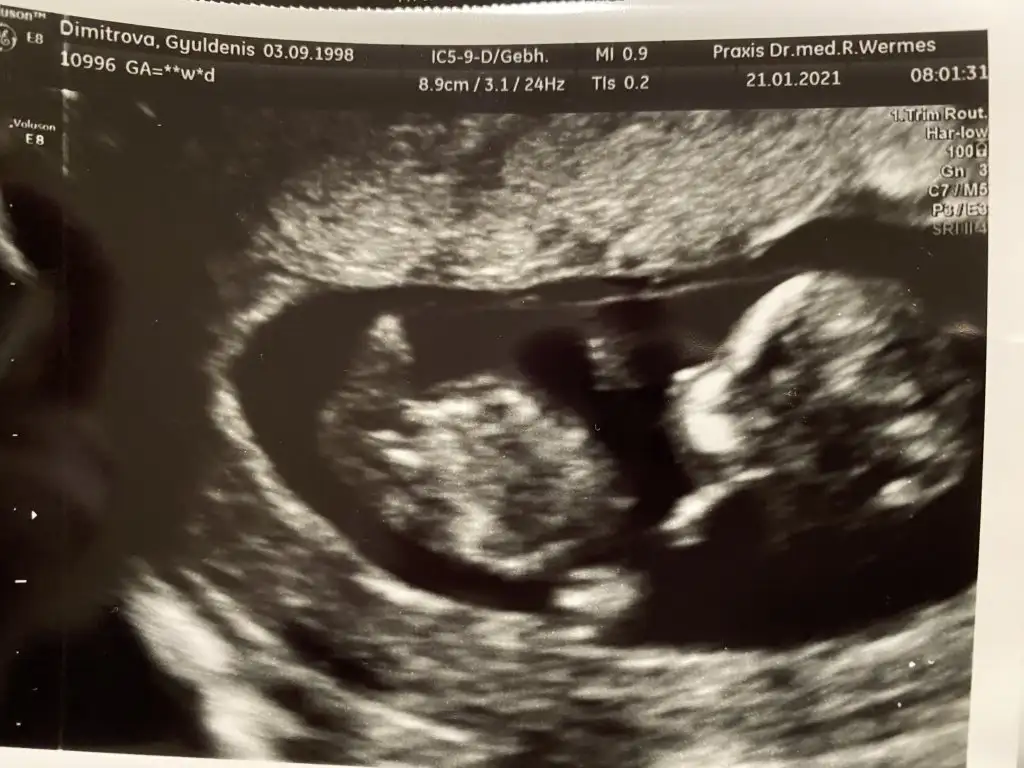

Kiz erkek aslinda fark etmiyor ama yavrumu severken ona kizim ya da oglum demek icin merak ediyorum 🥰😘

Eklentiler

• 4EE500F0-30DB-4F63-BD85-B5CF32B42DEE.webp

4EE500F0-30DB-4F63-BD85-B5CF32B42DEE.webp

43,6 KB · Görüntüleme: 182